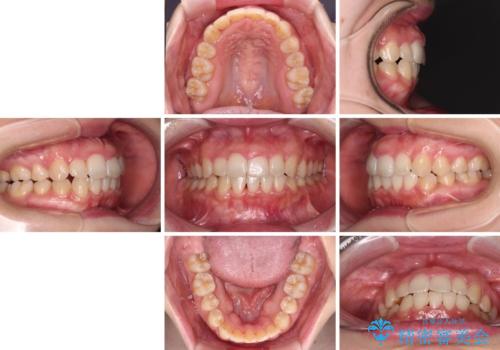

変則的な抜歯となるため、正中と人中がずれる可能性がありましたが、仕上がりは上下正中を揃えることができました。